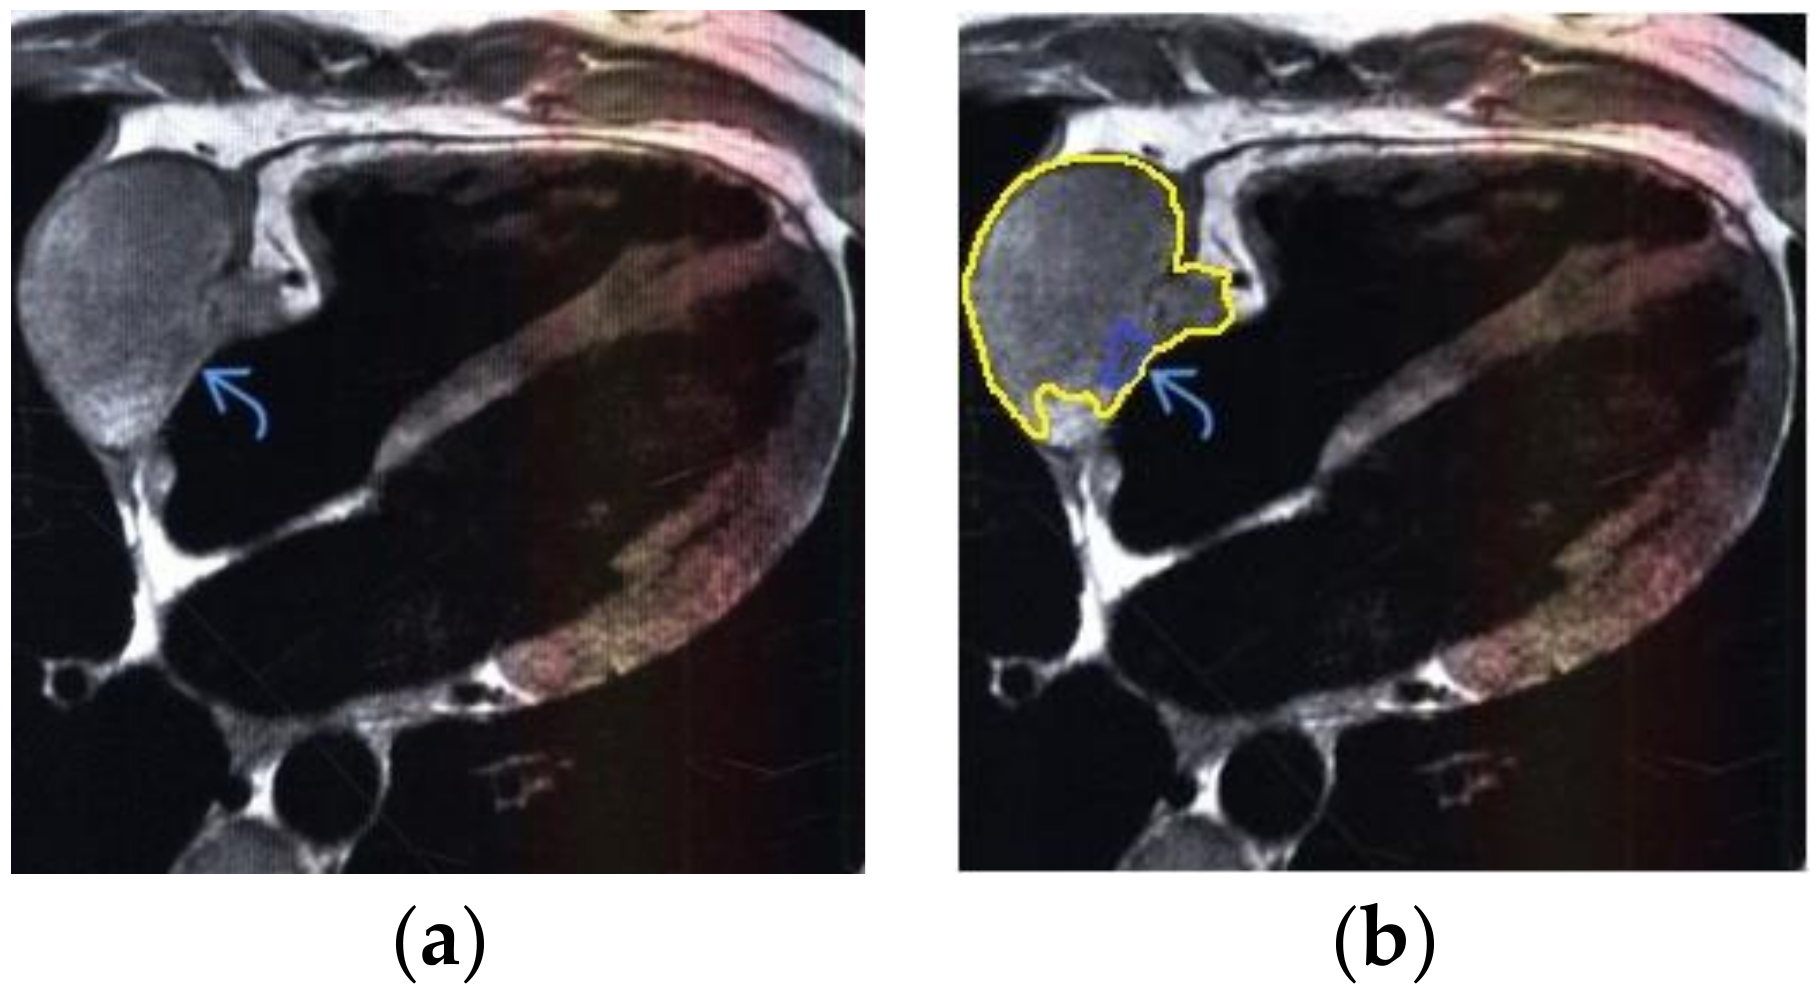

The contour extraction method was used to identify cancerous areas that, after applying the model to eliminate mixed noise, had an increased contrast of volumetric heterogeneous formations in the region of the heart [27]. This method was developed by the authors when analyzing thermal images to assess the condition of the coronary vessels of the myocardium under cardiopulmonary bypass. The contours of the cancerous regions in the examples used for applying the model to eliminate mixed noise (Figure 4, Figure 5, Figure 6, Figure 7, Figure 8 and Figure 9) are highlighted in yellow and they represent the visual boundary of the distribution of volumetric heterogeneous formations.

• For a patient with sarcoma of the heart: during MRI, a volumetric mass was determined in the lateral wall of the right atrium (Figure 7).

Applsci 10 04747 g006

Figure 7. Heart MRI: (a) image with white noise and (b) denoised image with contrast enhancement of sarcoma in the right atrium.

Applsci 10 04747 g007